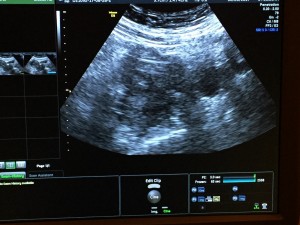

Once we got into the room, I was on a chair with my legs propped up (very similar to when you have your retrieval). The major difference is this time, you’re completely awake! Next, the x-ray tech came in and took some pictures of my cervix and uterus. Then Dr. Miller came in and was very jovial as usual! He said everything looked good, and proceeded to insert the catheter. This part made me feel a little crampy, but the feeling only lasted a minute so it wasn’t too bad – I would compare it to an intense pap. Then the embryologist brought our little embryo out in what looked like a really skinny straw. Dr. Miller inserted the skinny straw into the catheter, and voila, I’m pregnant (until proven otherwise)! Dan and I were able to watch everything on the x-ray screen. We couldn’t see the actual embryo since it’s microscopic, but we were able to see the air bubbles around it. It’s hard to tell in the picture below, but the embryo is the white speck in the middle of the picture. Dr. Miller reiterated that everything went as well as we could have asked for and wished us good luck!

Ultrasound image showing a grayscale scan of internal body structures, with various settings and measurement data displayed around the edges of the screen.